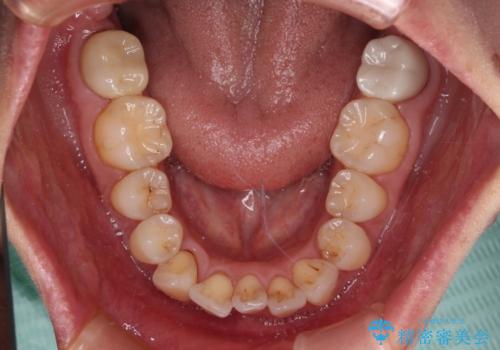

- 前方に飛び出した前歯を気にして来院された患者様です。

通常であれば上下左右の第一小臼歯4本を抜歯して口元の突出感を改善しますが、下顎前歯が1本欠損しており、上下の歯の数がアンバランスであるため、4本抜歯するかどうか悩むところでした。

上顎前歯はやや小さめで、下顎前歯はやや大きめであったため、上下左右4本を抜歯しても左右奥歯の咬み合わせは理想に近い状態を達成できると判断し、上下左右の第一小臼歯4本を抜歯し、ワイヤー装置にて矯正治療を行うこととしました。